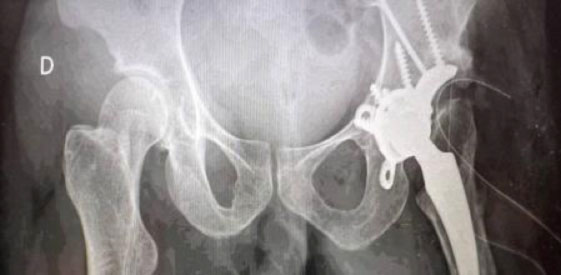

Las infecciones de prótesis articulares son una de las complicaciones más temidas y comunes de las cirugías de reemplazo articular, especialmente cuando se asocian a implantes protésicos utilizados en cadera y rodilla. El uso de la nanotecnología para el desarrollo de nuevos recubrimientos antimicrobianos constituye un ámbito importante de investigación para el tratamiento y profilaxis de infecciones de estas prótesis.